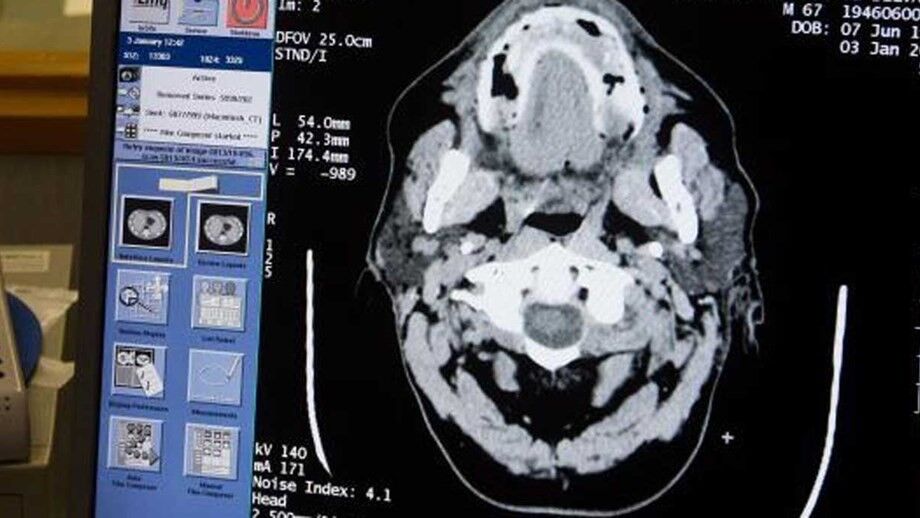

A Federação Inglesa de Futebol vai promover novas pesquisas para descobrir o que causa um maior risco de demência entre os jogadores profissionais, com 3,5 vezes mais probabilidade de morrer de doenças neurodegenerativas do que o resto da população.

Os riscos acrescidos para os futebolistas foram identificados em 2019 num estudo da Universidade de Glasgow e co-financiada pela Federação e pelo Sindicato dos Profissionais de Jogadores de Futebol.

Dois fatores potenciais para a demência podem ser os repetidos cabeceamentos na bola e as comoções.

Um grupo de trabalho está a considerar possíveis recomendações para se evitarem toques de cabeça durante os treinos profissionais; os técnicos já são desaconselhados a evitá-los nas camadas mais jovens.